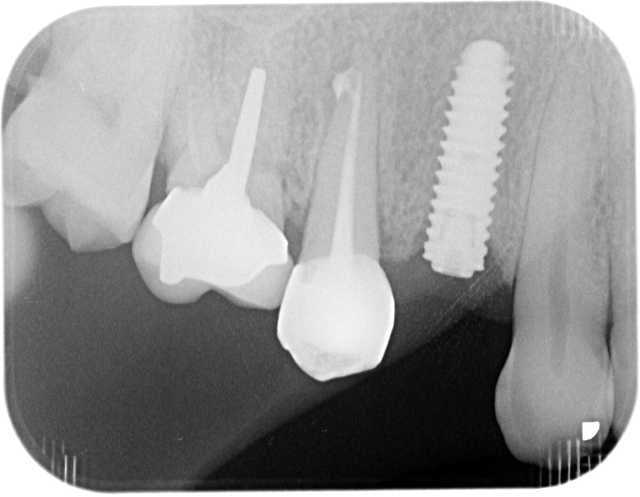

pour la forme et le fond pano avant retro à la pose et rétro aujourd'hui

prévu implant en 36 et l'endo de 15 avait été reprise avant pour être refaite simultanément je connais les critiques nonoliennes.

pour info déja trois cas similaires au maxillaire pas à la mandibule.

et c'est un axiom en 4*12 pas un krestal